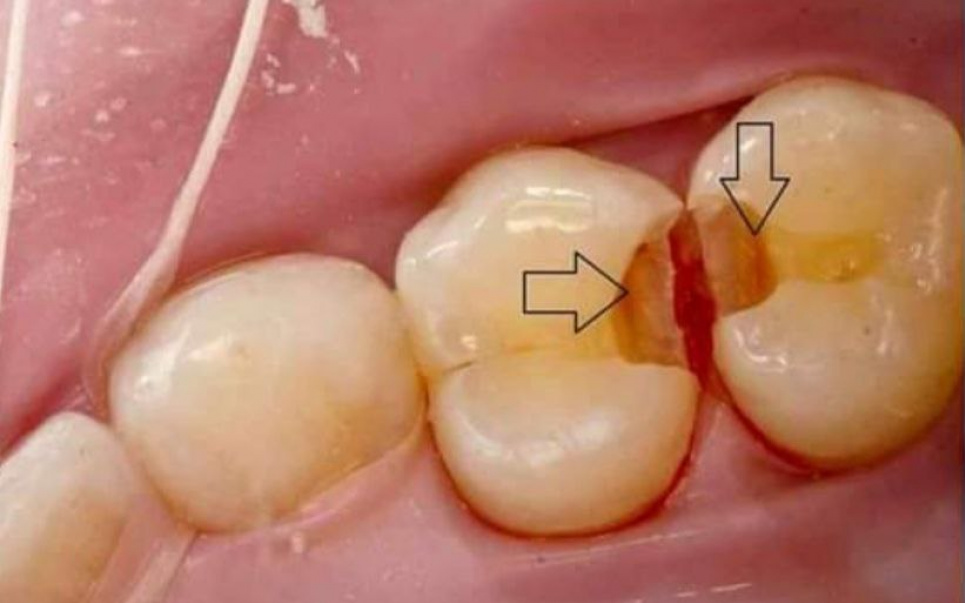

Карієс, який «цілується», називається міжзубним і насправді може вражати не два, а цілу групу зубів, розповідає «Стоматологія по-простому». Такий карієс складно побачити навіть на огляді: він вибирає затишне місце, куди не дістати щіткою або йоршиком. А при сильній скупченості зубів не вийде дістати навіть іригатором і зубною ниткою, та й на професійному чищенні можуть виникнути проблеми.

Такий карієс найчастіше розташовується з внутрішньої сторони зуба, ближче до ясна. Зверху зуб виглядає здоровим. Бічні поверхні зубів стикаються, і він підступно переходить із одного на інший.